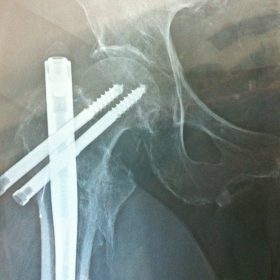

Διατροχαντήριο : Εξωαρθρικό κάταγμα, στην περιοχή ανάμεσα στο ελάσσονα και το μείζονα τροχαντήρα. Αντιμετωπίζεται χειρουργικά με ενδομυελική ήλωση τύπου γ-Nail. Δύο τομές 3 εκατοστών και 1 εκατοστού αντιστοίχως για την εισαγωγή και το κλείδωμα του ήλου μέσα στο οστό. Η μέθοδος είναι κλειστή,σχεδόν αναίμακτη,διάρκειας 30 λεπτών,με τη βοήθεια C-ARM (τηλεόρασης). Στον ασθενή παρέχεται οπτικό υλικό (όλα τα χειρουργικά στάδια) σε CD ή Στικάκι,λόγω της δυνατότητας καταγραφής του χειρουργείου από το C-ARM Ο ασθενής περπατάει άμεσα μετεγχειρητικά στις 5 ώρες μετά την επέμβαση και εξέρχεται από το νοσοκομείο σε 1 -2 ημέρες.